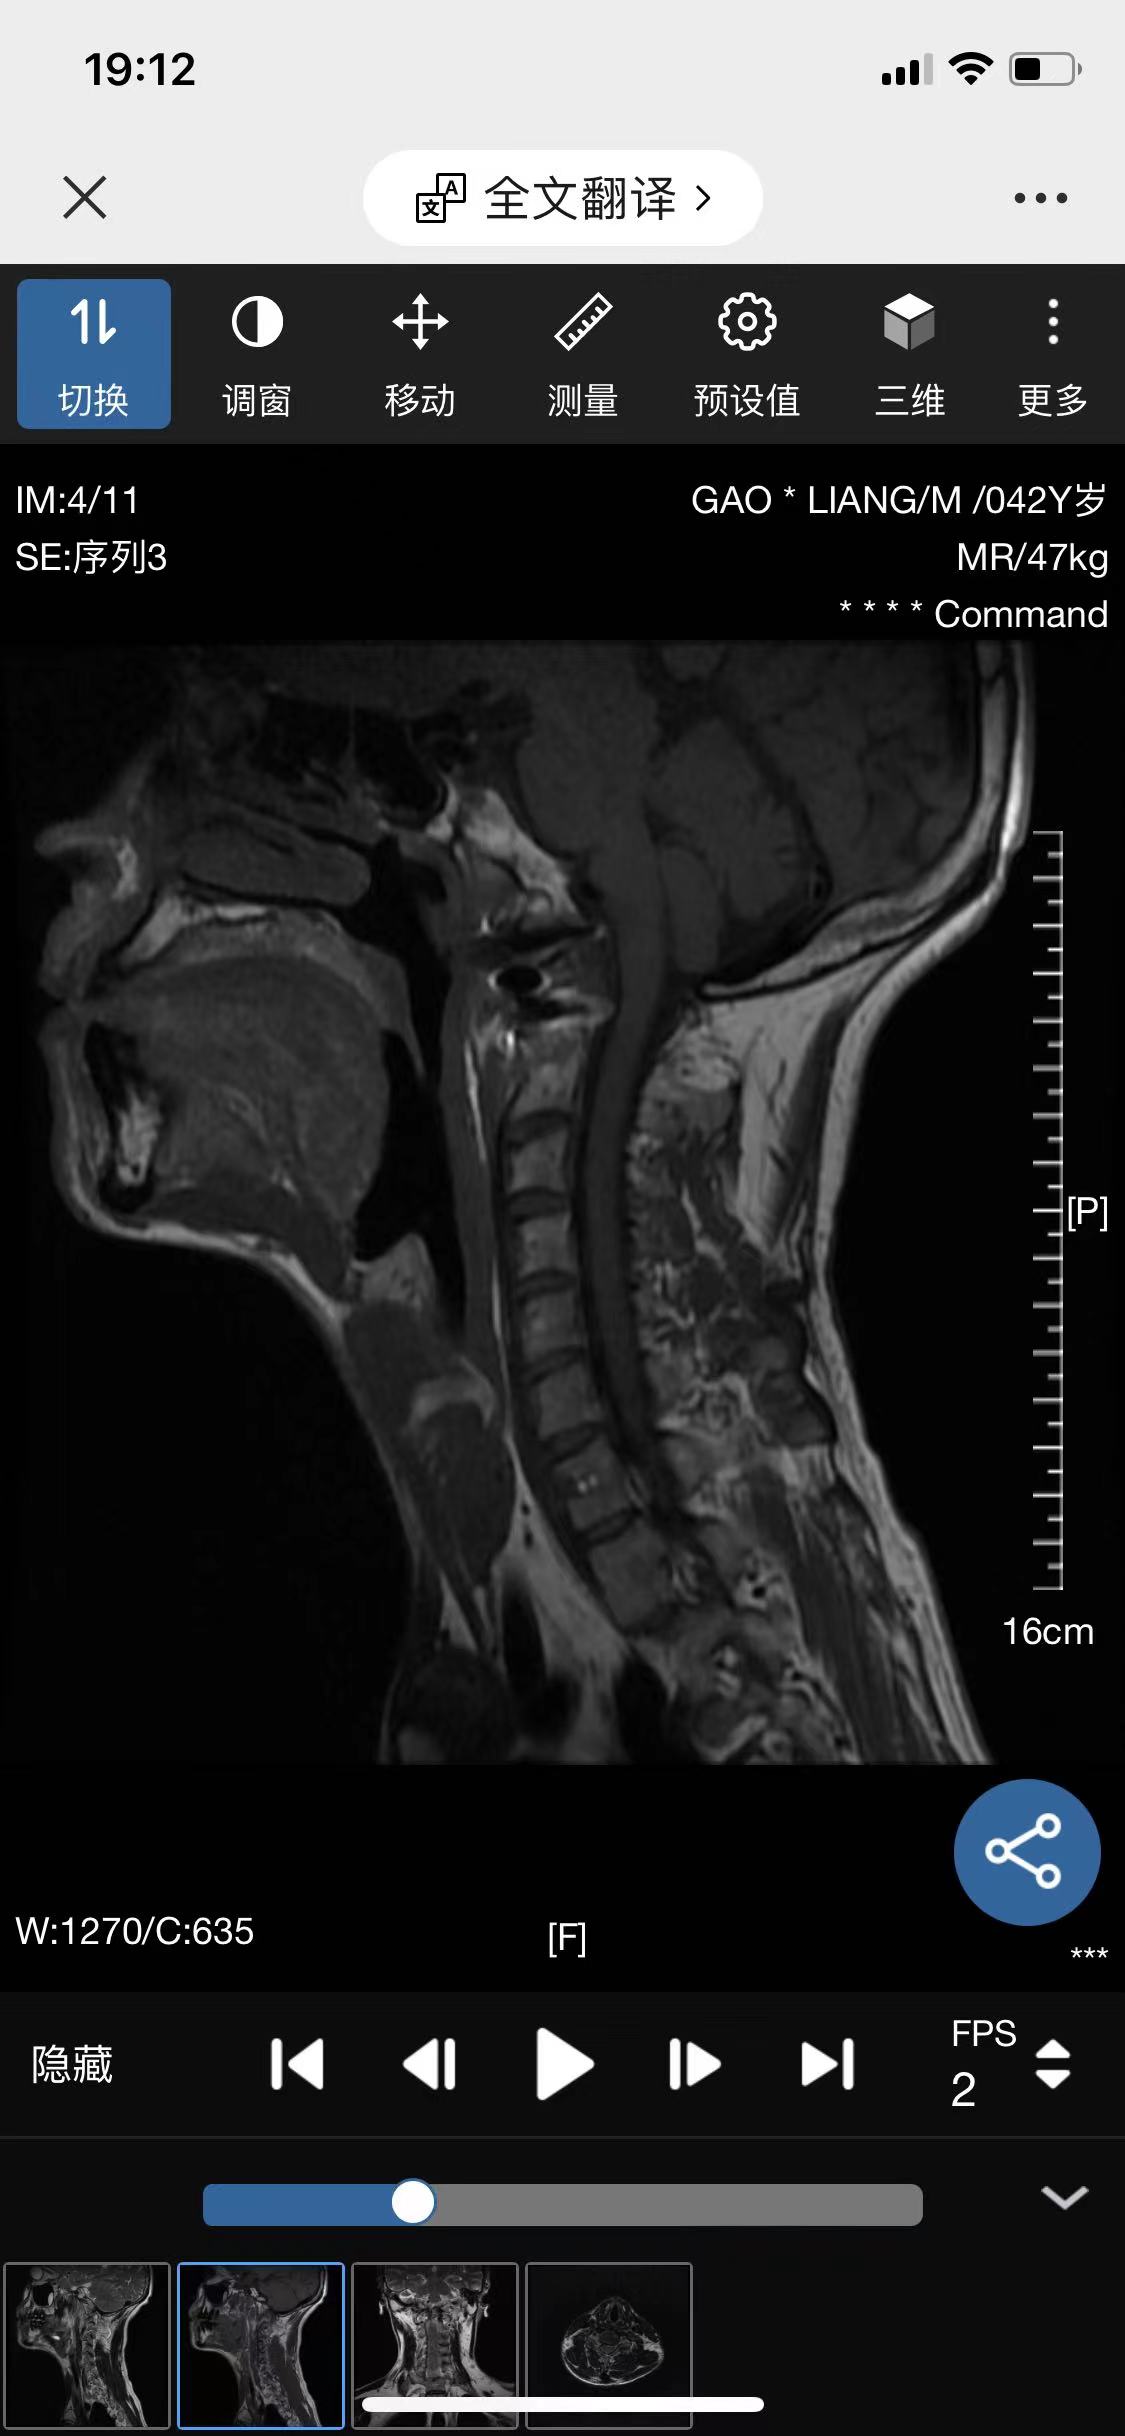

• 诊断:寰枢椎脱位

• 影像:

• 术后影像: